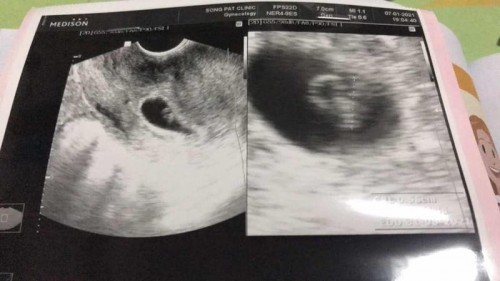

ท้องสองเดือนกว่าค่ะ มีอาการปวดเอวด้านล่างขวาเวลานอน

แม่ๆๆค่ะ น้องขอสอบถามหน่อยค่ะ น้องท้องนอกมดลูก แล้วตัดรังไข่ข้างซ้ายออก เมื่อเดือน ก.พ.63 ค่ะ ตอนนี้ท้องได้ 2 เดือนแล้วค่ะ น้องไปฝากท้องตอน 6 วีค ตอนซาวเจอแค่ถุงตั้งครรถ์ค่ะ น้องมีอาการปวดเสียวตรงเอวข้างขวาค่ะ เวลานอแต่ไม่ได้ปวดทั้งวันค่ะ จะมีหน่วงๆๆท้องน้อยบ้างบางวันค่ะ ตั้งแต่รู้ตัวว่าท้อง แพ้ท้องหนักมาค่ะ จนผ่านมาสองเดือนกว่าอาการแพ้ค่อยๆๆหายค่ะ น้องเครียดค่ะ ไม่รู้ผิดปกติหรือป่าว คุนหมอนัดอีกที4 ก.พ.ค่ะ